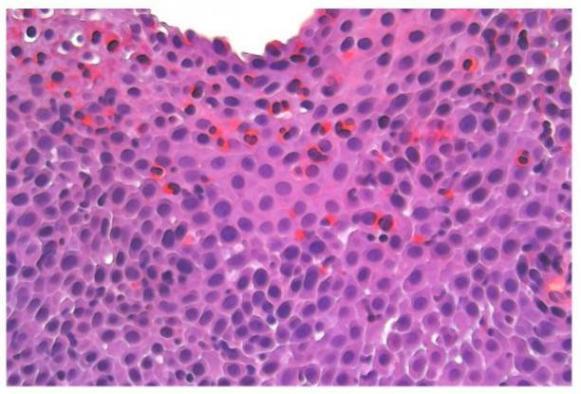

Global Eosinophilic Esophagitis Market Study 2021-2032, by Segment. A new Eosinophilic Esophagitis market research report that keenly observes the 2022 industry and gives a diligent idea regarding the current market, latest market movements, future goals and directions, and regulatory panorama. The report Eosinophilic Esophagitis market provides highlighting new business opportunities and...